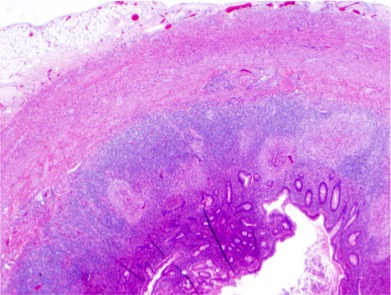

Case Presentation: A 22-year-old Hispanic male presented with a 4 day history of rectal and abdominal pain. He denied any previous medical history. He also noted three months of productive cough, pyrexia, chills, night sweats, fatigue, and weight loss. Physical examination revealed right lower quadrant tenderness accompanied by abdominal rigidity and involuntary guarding. The patient declined digital rectal examination. Labs were normal. Chest xray revealed biapical pleural thickening associated with parenchymal scarring, bronchiectasis, nodularity, and and superimposed infiltrates. CT of the abdomen revealed acute appendicitis and a peri-rectal abscess. The patient underwent laparoscopic appendectomy and drainage of the peri-rectal abscess. This was followed by bronchoscopy with BAL. Sputum, BAL, and cultures from peri-rectal abscess were positive for acid-fast bacilli. Histologic examination of the appendix revealed granulomatous inflammation with central necrosis, multi-nucleated giant cells, and acid-fast positive bacilli confirming tuberculous enteritis.

Discussion: Mycobacterium Tuberculosis (TB) is the second most common infectious cause of death worldwide. It may manifest in any organ system and mimic many different diseases. The respiratory system is most commonly affected. When the gastrointestinal system is involved, it is referred to as tuberculous enteritis. The ileocecum is most often affected with appendicular involvement a rare occurence. There are four main mechanisms which may lead to tuberculous enteritis. These include swallowing of infected sputum in active pulmonary tuberculosis, ingestion of contagious milk from cattle infected with bovine TB, direct extension from adjacent organs, and hematogenous spread. Once the bacillus enters the gastrointestinal, tract it traverses the mucosa to lodge in the submucosa leading to inflammatory changes including cellular infiltration, lymphatic hyperplasia, serosal, and submucosal edema. The eventual result of inflammation is production of granuloma which causes small papillary mucosal elevations, lymphangitis, endarteritis, and fibrosis. In due course mucosal ulceration develops along with caseating necrosis, and narrowing of the intestinal lumen leading to obstruction. We believe this patient may have either ingested sputum from active TB or he developed hematogenous spread from the pulmonary focus. Fortunately he presented earlier on in the disease process. He was started on Rifampin, Ethambutol, Isoniazid, and Pyrazinimide and achieved convalescence with further surveillance tests at different time intervals returning negative.